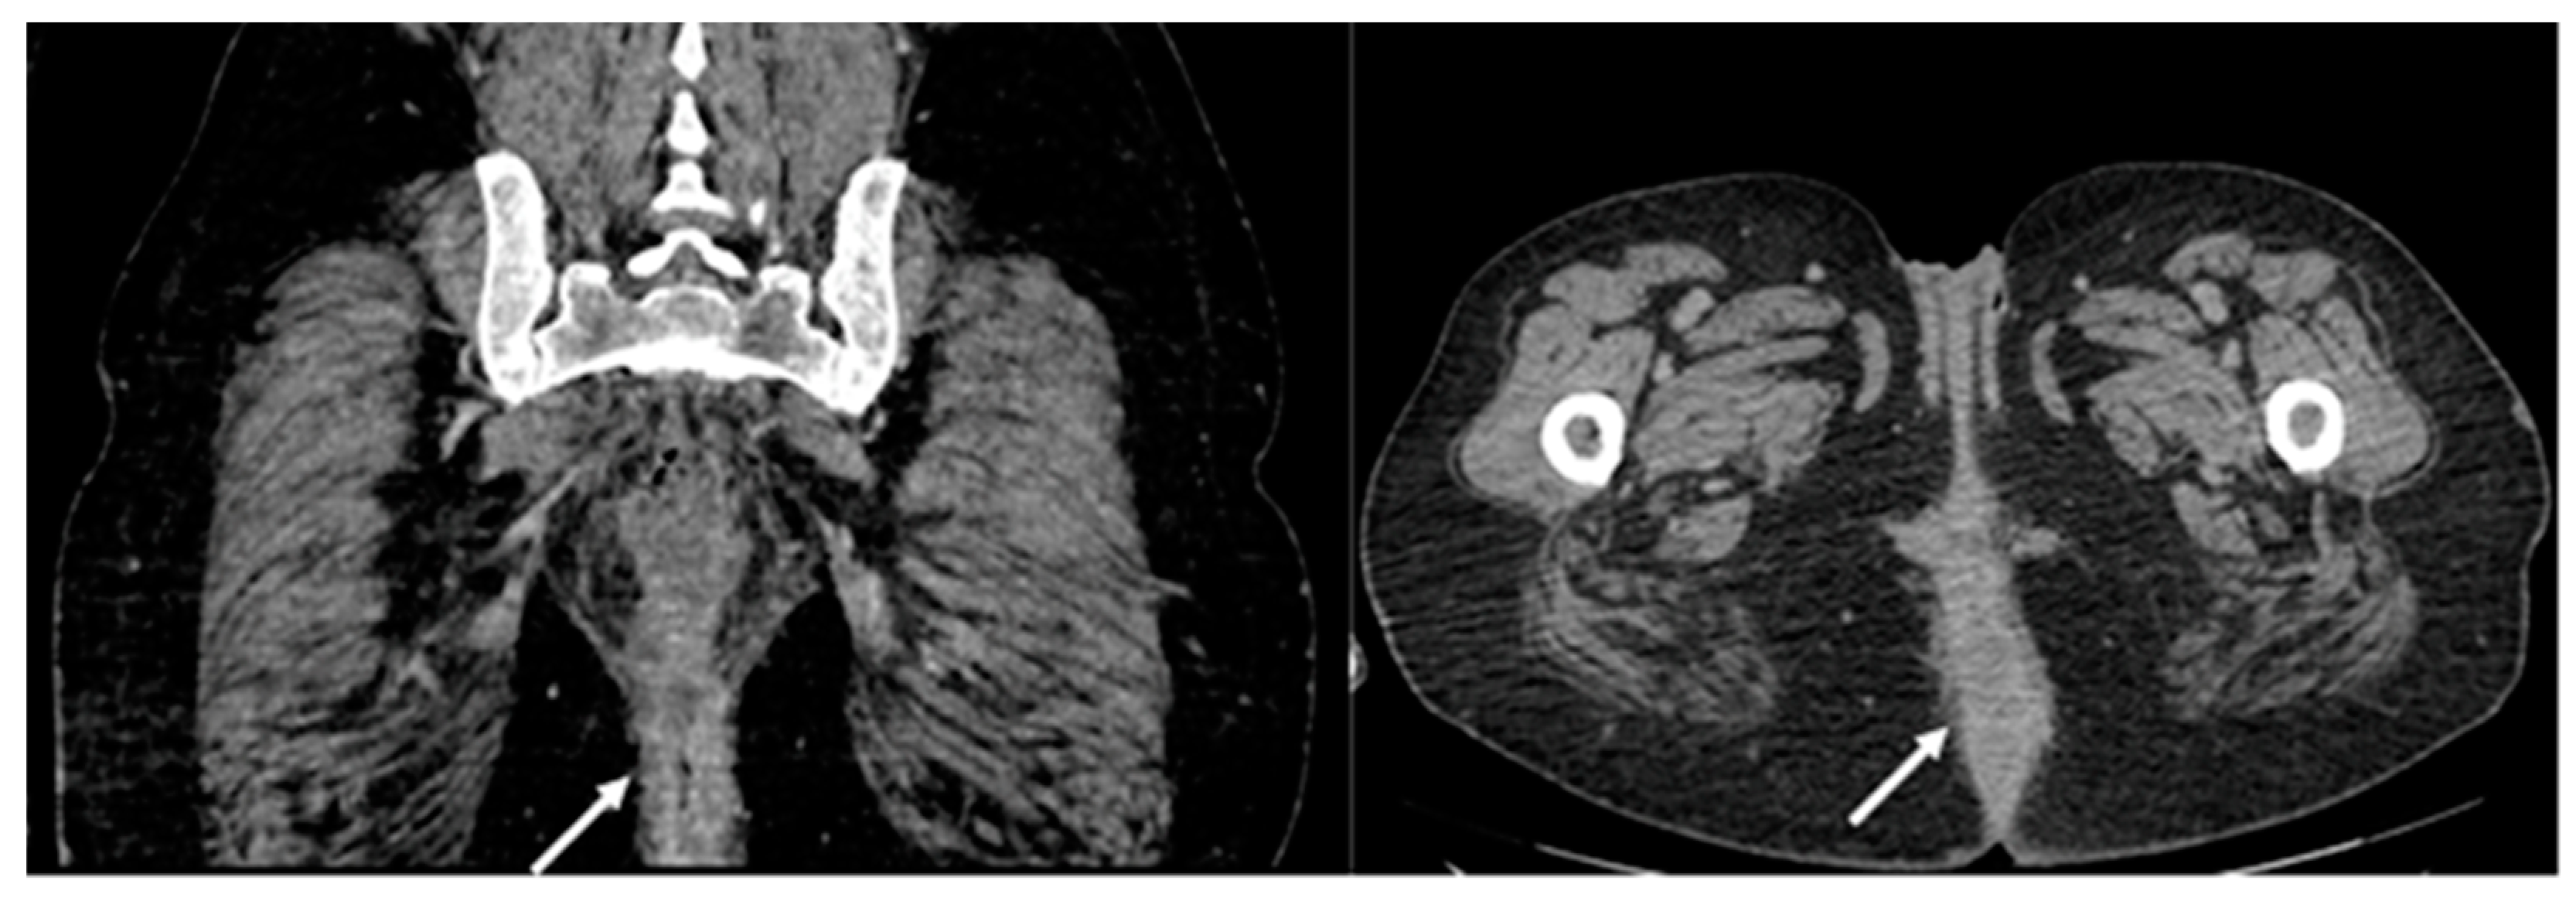

2.1. Case Report